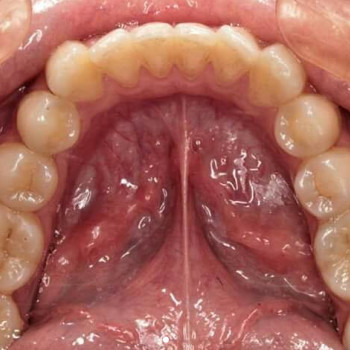

Сергій Руденко (Хмельницкий) Стоматолог

Сергій Руденко

Лікую те, що більшість видаляє